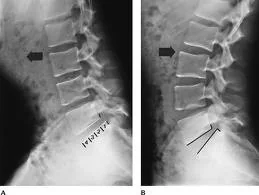

A radiografia simples pode ser um exame de rotina para dores lombares em geral, porém possui baixa definição para o diagnóstico de hérnias de disco. Pode ser útil em casos de dúvida quanto ao nível afetado, ou para investigar instabilidade com radiografias dinâmicas em flexão e extensão.

Radiografias dinâmicas da coluna lombar em flexão e extensão

Radiografias dinâmicas da coluna lombar: (A) em flexão. (B) em extensão.